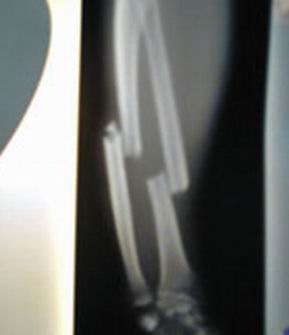

为了使骨折处愈合,现在医生常采用各种人造嵌入物,这些人造嵌入物用螺钉固定。人造嵌入物不仅仅是固定两部分折断的骨骼,而且是有助于骨骼的生长,但是这一效果并不好,存在材料排异反应的危险。

哈顿博士及其同事的研究开辟了治疗骨折的新途径,只要简单地注射纳米管溶液,然后即可观察到新骨组织是如何快速生长。确实,普通纳米管在体内工作得并不好,而用附加化学物质专门处理过的改型纳米管却十分出色,且没有材料排异反应的危险。